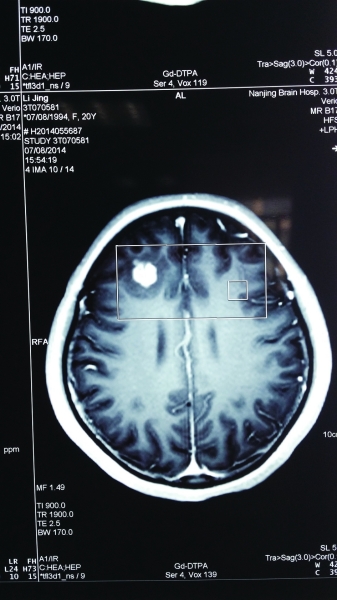

CT扫描显示,小静脑中高亮处疑是寄生虫。

来自淮安的20岁的女大学生小静(化名),因晕倒、抽搐等症状入院,起初都被当做癫痫治疗。南京脑科医院的专家,怀疑是寄生虫入脑,在手术当中,医生取出了一个3厘米长的白色虫子,放在托盘上的虫子还在动!据介绍,这是猪肉绦虫幼虫,怀疑小静是吃到了被污染的食物造成的感染。专家表示,预防寄生虫病,关键还是要注意饮食卫生和个人卫生,饭前便后要洗手;不食生的或半生的肉品,生熟砧板分开。